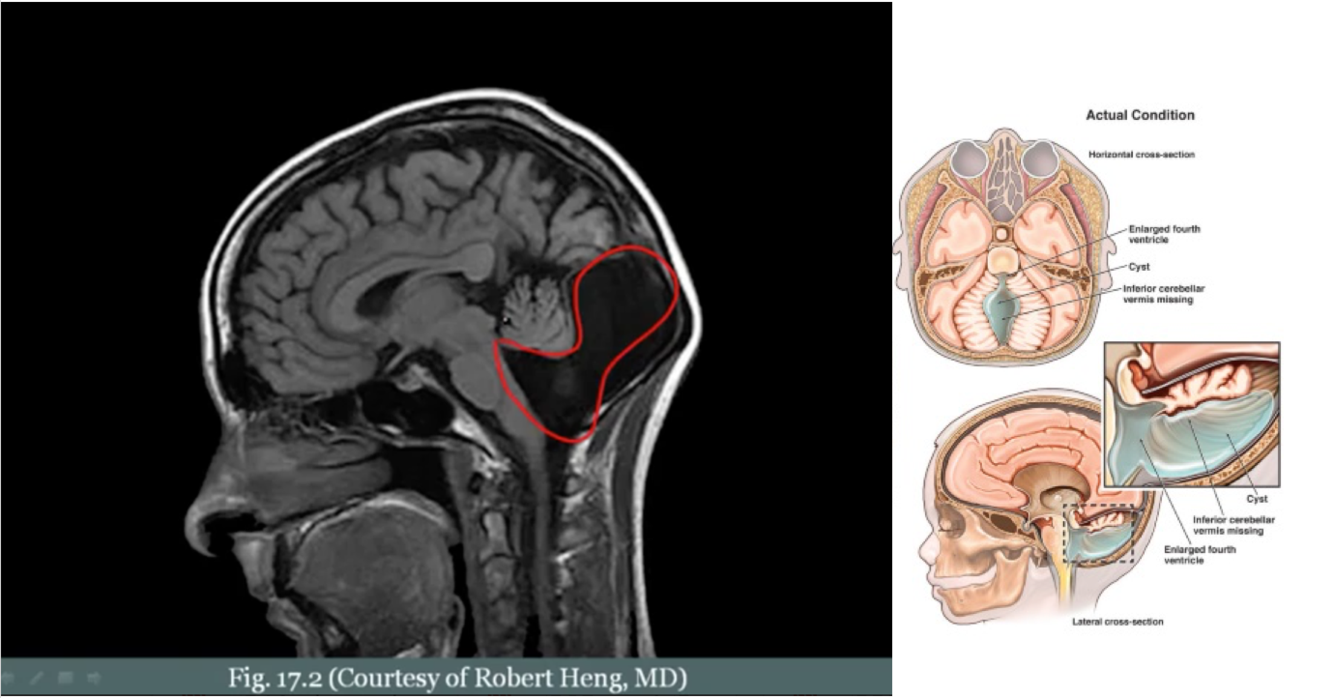

What is Dandy-Walker malformation? What does it cause?

Congenital failure of the cerebellar vermis to develop. The vermis is what separates/connects the two sides of the cerebellum.

Dilation of the 4th ventricle (no vermis, 4th ventricle can expand)